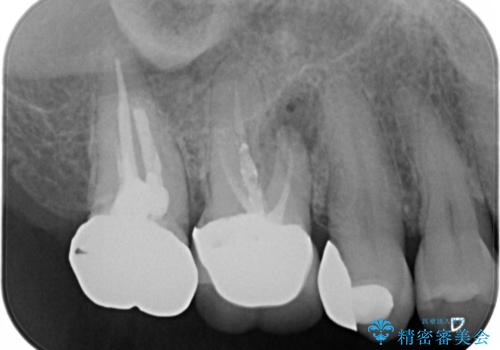

- 元々は別の部位の治療で通われていた患者様でしたが、ニキビのようなものが繰り返しできたり消えたりするとのことで、治療介入を行いました。

根管治療を再度行うことでフィステル(ニキビのようなできもの)は消失しました。最終的にセラミッククラウンによる補綴治療を行いました。